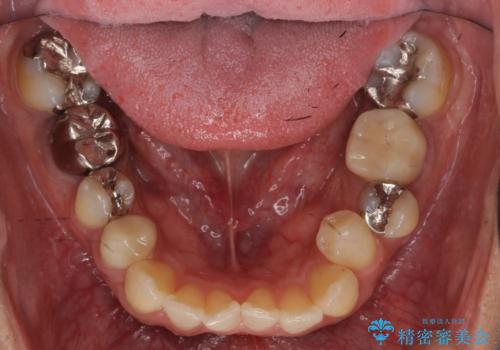

虫歯がひどく抜歯 奥歯をブリッジに

- 全体を見て欲しいと来院。

右下の奥歯の虫歯が大きく、やりかえが難しい状態でした。

外して虫歯を取ったところ。歯茎の深いところまで虫歯があり、やむなく抜歯しました。

右下7については、遠心の歯の高さがなく、また、同様に歯肉縁下にカリエスがあったため、手術を行い改善しました。